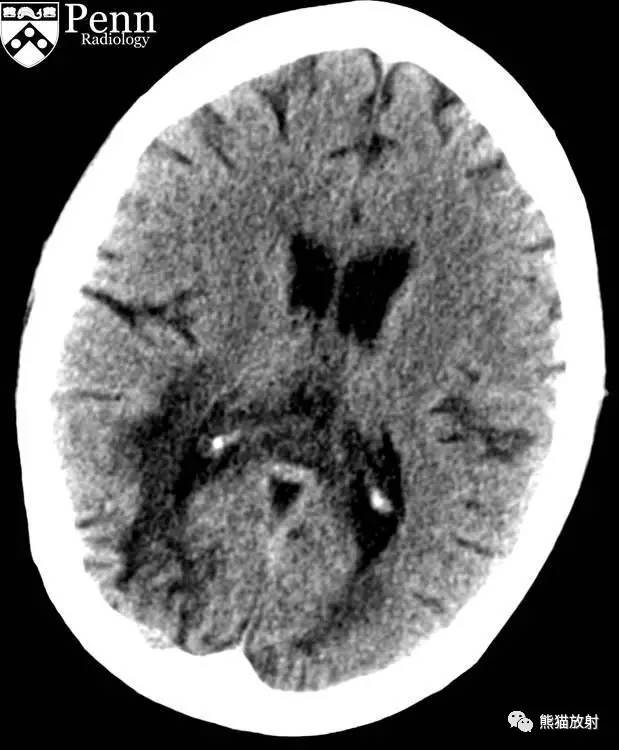

CASE 1

病史:47岁男性,最近诊断为HIV感染,CD4计数为50,精神状态异常。

CT平扫表现:左额叶白质见片状低密度,经胼胝体累及右额叶白质。